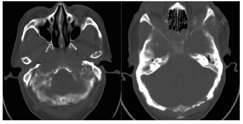

患者既往体健,查体:贫血貌,皮肤、巩膜无黄染,头部视诊外形不规则,可触及多个肿物,最大约6 cm×6 cm,质硬,无压痛,表面光滑,活动度差。右颈部、左锁骨上窝及双侧腋下、腹股沟可触及多枚肿大淋巴结,为黄豆到蚕豆大小不等,均质硬,无压痛,表面光滑,活动度差,与周围组织分界尚清。胸骨无压痛,心脏查体未见异常,双下肺听诊呼吸音减弱,左侧为著,腹软,无压痛、反跳痛及肌紧张,肝脏触诊肋下3 cm,脾脏触诊肋下4 cm,表面光滑,无触痛。实验室检查:WBC 7.63×109/L(外周血涂片淋巴细胞比例0.46,淋巴细胞绝对值计数3.5×109/L),血红蛋白74 g/L,红细胞平均体积(MCV)100.4 fl,红细胞平均血红蛋白浓度(MCHC)306 g/L,血小板计数(Plt)62×109/L,清蛋白37.3 g/L,血清乳酸脱氢酶267 U/L,β2微球蛋白5.44 mg/L,肾功能正常,血钙3.10 mmol/L,胸腔积液乳酸脱氢酶198 U/L,血清IgA、IgM轻度降低,血、尿免疫固定电泳、血游离轻链检测、血清蛋白电泳、肿瘤标志物均未见异常。颅脑CT示:可见颅骨多发溶骨性损害,双侧颌面骨、颅骨多发骨质改变及双侧眼外上方、双侧鼻窦、乳突内异常密度影(图1)。肺部多排CT平扫示:纵隔内、心前间隙及左侧腋窝多发淋巴结肿大,后下纵隔脊柱周围、左侧胸腔内、左侧前胸壁多发软组织肿块,均考虑恶性占位性病变。同时双侧胸腔积液及骨性胸廓改变。胸椎正侧位数字化X线摄影(DR)示第1~12胸椎轻度骨质增生,椎体密度减低。腰椎正侧位DR示第3~5腰椎骨质增生。腰1~5椎体骨质密度减低。腹部超声可见肝、脾及肝门处腹腔淋巴结肿大(大小约19 mm×11 mm)。浅表淋巴结超声可见双侧颈部、锁骨上窝、腋下及腹股沟均可见不同程度肿大淋巴结(大小约在7 mm×6 mm~37 mm×13 mm)。骨髓涂片示:有核细胞增生活跃,淋巴细胞占0.925,其中浆细胞样淋巴细胞占0.915。胞体小,胞质量中等,呈泡沫状。外周血片示:淋巴细胞比例增高,占46%,其中浆细胞样淋巴细胞占25%,成熟红细胞缗钱样排列,血小板成簇可见。中国医学科学院血液学研究所骨髓活组织检查HE染色示骨髓组织中可见异型淋巴样细胞增生伴纤维化,免疫组织化学示异型淋巴细胞CD5+、CD20+、CD23+、PAX5+、CD138-、CD3-、CD10-、cyclin D1-,符合CLL/B小淋巴细胞淋巴瘤免疫表型。外周血、胸腔积液细胞流式分型也支持CLL表型。骨髓荧光原位杂交技术(FISH)未检测到IGH/CCND1融合基因、D13S25、TP53基因缺失以及ATM、CEP12基因异常。头部肿物活组织检查免疫组织化学结果示:Ki-67(10%+)、CD5+、CD20+、CD23+、PAX-5+、bcl-2+、CD38-、CD138-、CD3-、CD10-、cyclin D1-、bcl-6-、CD21-、MPO-。左侧腋窝淋巴结活组织检查免疫组织化学结果示:Ki-67(10%+)、CD5+、CD20+、CD23+、PAX-5+、CD43+、bcl-2+、MUM-1+、κ(部分+)、CD38-、CD138-、CD79a-、CD3-、CD10-、cyclin D1-、bcl-6-、CD21-、CD56-、λ-,亦支持CLL/B小淋巴细胞淋巴瘤诊断。